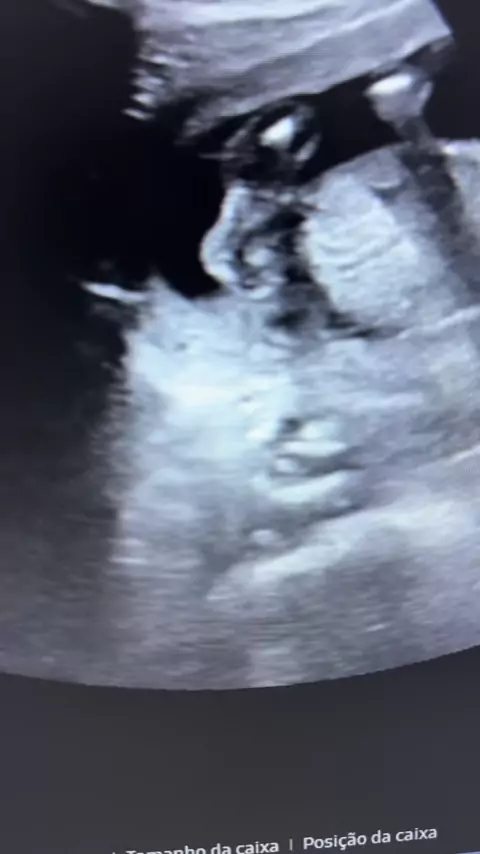

💍 SINAL DO ANEL DE BRILHANTE NA GESTACAO INICIAL O sinal do anel de brilhante é um achado muito importante no inicio da gravidez. Ele indica que a gestacao é topica, ou seja, esta dentro do utero, e que esta tudo bem com o bebe. O anel representa a vesicula do saco gestacional e o brilhante representa o embriao. Essa imagem mostra que a gravidez esta bem posicionada e com boa evolucao inicial. 📸 Um achado simples no ultrassom que traz muita tranquilidade para a mae e para o medico. #gestacao ...